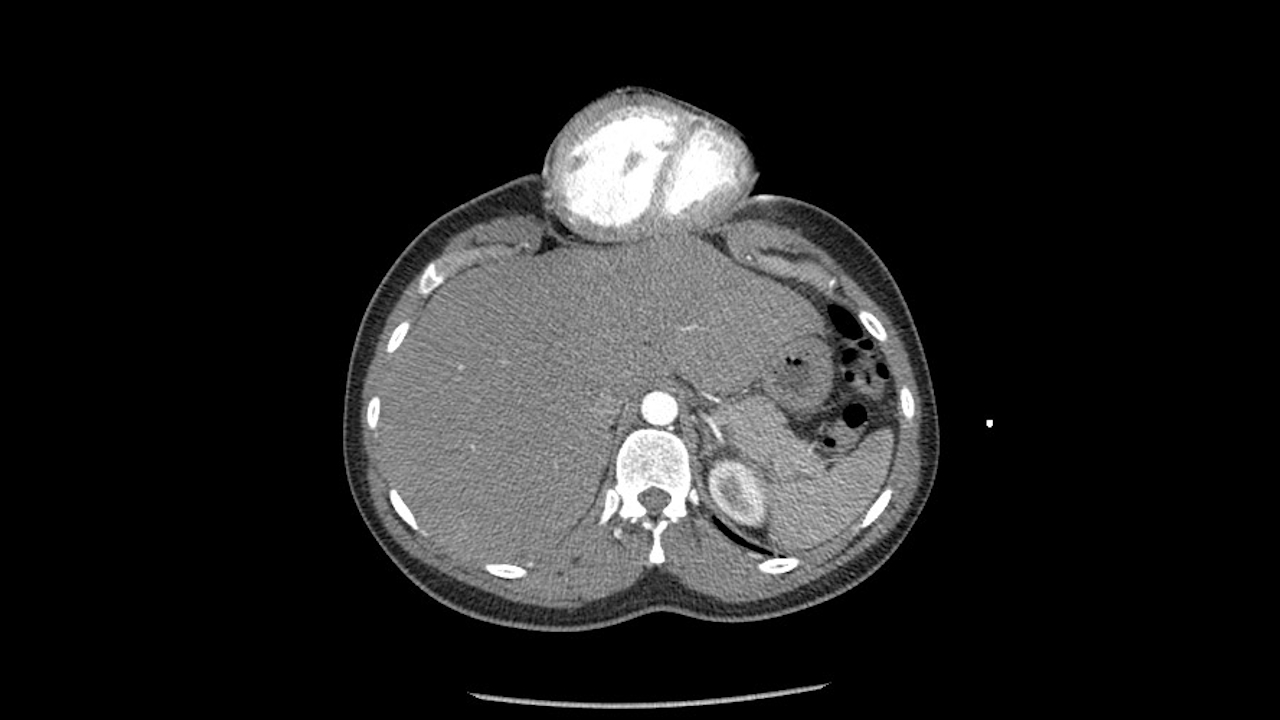

Знімок МРТ іншої дитини з цією ж патологією: серце знаходиться за межами грудної клітини, а частини груднини немає. Radiopaedia.org